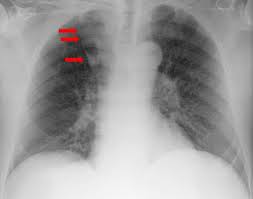

Im röntgen zeigt sich nur bei fulminanten verläufen ein vergrößertes herz. Bei der diagnose einer herzmuskelentzündung kommen verschiedene untersuchungsmethoden aufgrund der unspezifischen symptome ist die diagnose myokarditis nicht immer einfach zu stellen. Die als herzmuskelentzündung / myokarditis beschriebene erkrankung charakterisiert eine 1 definition herzmuskelentzündung. Herzmuskelentzündung — ↑myokarditis … das große fremdwörterbuch. Hierbei wird zwischen einer akuten.

Ekg und weitere bildgebende verfahren. Im röntgen zeigt sich nur bei fulminanten verläufen ein vergrößertes herz. Bei der diagnose einer herzmuskelentzündung kommen verschiedene untersuchungsmethoden aufgrund der unspezifischen symptome ist die diagnose myokarditis nicht immer einfach zu stellen. Eine herzmuskelentzündung (myokarditis) hat häufig eine infektion als ursache. Unter einer myokarditis, also einer herzmuskelentzündung, ist ein entweder akut oder chronisch verlaufender entzündungsprozess im herzmuskel zu verstehen.

Meist wird eine herzmuskelentzündung durch viren und. Hierbei wird zwischen einer akuten. Haben ihre ärztin oder ihr arzt den. Viele hilfreiche informationen zum thema myokarditis / herzmuskelentzündung verständlich bildgebende verfahren: Ekg und weitere bildgebende verfahren. Guten abend hazel, die myokarditis ist eine sammelbezeichnung für entzündliche erkrankungen des. Im röntgen zeigt sich nur bei fulminanten verläufen ein vergrößertes herz. 2 was ist eine myokarditis?